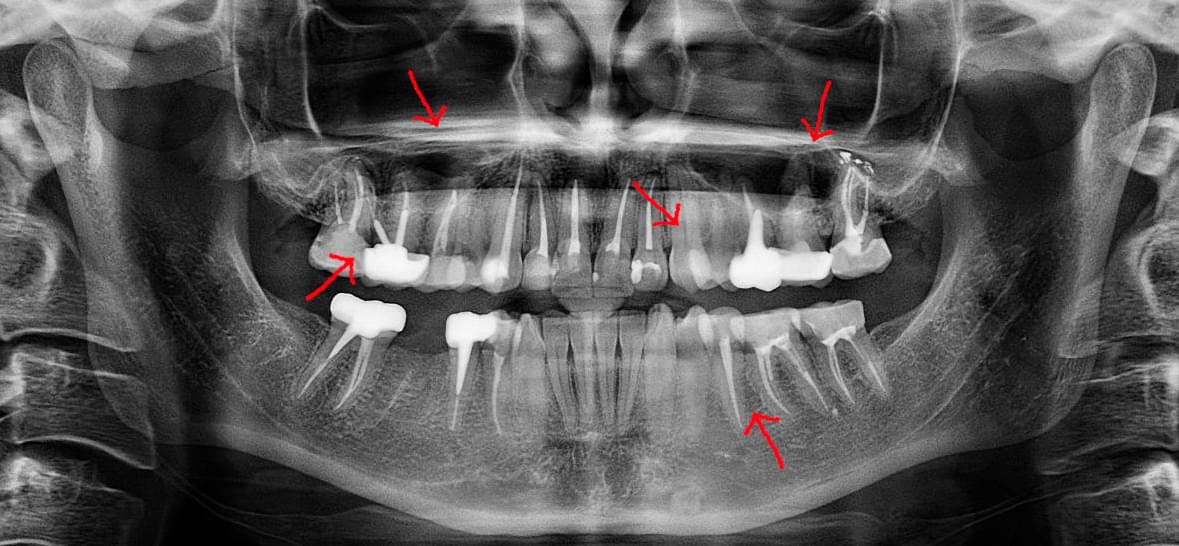

Головний недолік 2D-рентгену — це площинне зображення. Зуби, корені, щільна кістка та гайморові пазухи накладаються один на одного, створюючи «візуальний шум».

При плануванні імплантації лікарю важливо знати дві речі: об'єм кістки та точне розташування нервів.

КТ дозволяє провести віртуальну операцію: встановити імплант у програмі, виключивши будь-які ризики травмування пацієнта.

Часто причиною зубного болю є гайморит, і навпаки — причиною запалення пазух є хворий зуб. На звичайному знімку пазуха виглядає як темна пляма. На КТ ми бачимо стан слизової, наявність кіст або сторонніх тіл (наприклад, залишків пломбувального матеріалу), що критично важливо для правильного діагнозу.